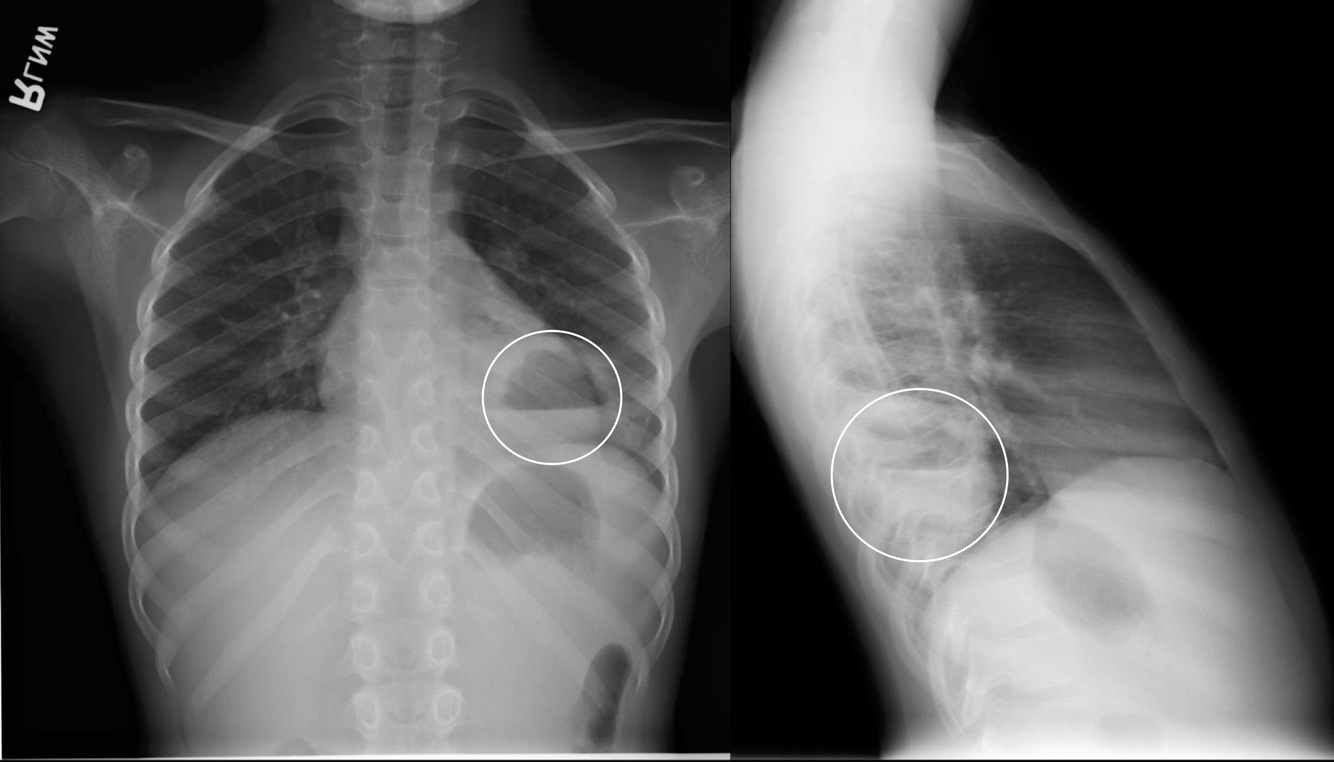

CXR: Complicated PNA with pleural involvement.

Empyema

Pus within the pleural cavity.

Pleural Effusion

Fluid within the pleural cavity.